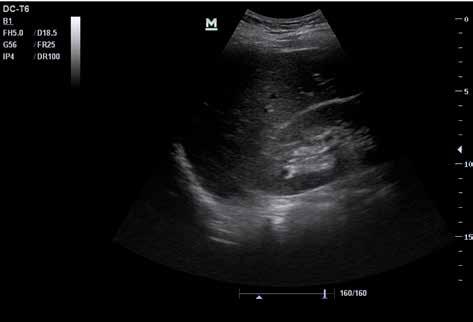

Abb. 34 ˘ Morison-Pouch (1) zwischen Leber (2) und rechter Niere (3). Rechtsseitiger Flankenschnitt 1 2 3

Abb. Abb.

44 4 ˘ Pathologische Befunde

36 ˘ Douglas-Raum (1) dorsal der Blase (2). Unterbauchlängsschnitt

35 ˘ Koller-Pouch (1) zwischen Milz (2) und linker Niere (3). Linksseitiger Flan kenschnitt 3 2 1 21

Zunächst sammelt sich mögliche freie Flüssigkeit an drei typischen präformierten Stel len im Bauchraum und kann hier sonografisch dargestellt werden. Dies sind der MorisonPouch, der Koller-Pouch und der Douglas-Raum (von engl. „Pouch“ für „Beutel“, Abb. 34 –36).

Der Morison-Pouch ist eine Aussackung des Peritoneums zwischen Leberunterrand und rechter Niere. Dem entspricht auf der Gegenseite der Koller-Pouch zwischen Milz und linker Niere. Der Douglas-Raum befindet sich dorsal hinter der Harnblase und zieht bis ins kleine Becken.

Abb. 37 ˘ Freie Flüssigkeit (FAF) (1) im Morison-Pouch. Rechtsseitiger Flankenschnitt Abb. 38 ˘ Freie Flüssigkeit (FAF) (1) im Koller-Pouch. Linksseitiger Flankenschnitt

46 4 ˘ Pathologische Befunde

1 1